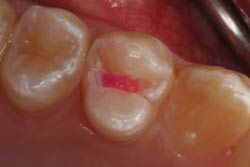

Для чёткого определения границ вмешательства нами используется препарат, именуемый кариес-детектором. Принцип работы заключается в следующем: на предварительно отпрепарированную полость на 1 минуту наносится специальный раствор (кариес-детектор).

Участки, подверженные деминерализации, окрашиваются, что помогает врачу не пропустить ни одного поражения, и вместе с тем бережно отнестись к участкам здоровой эмали.